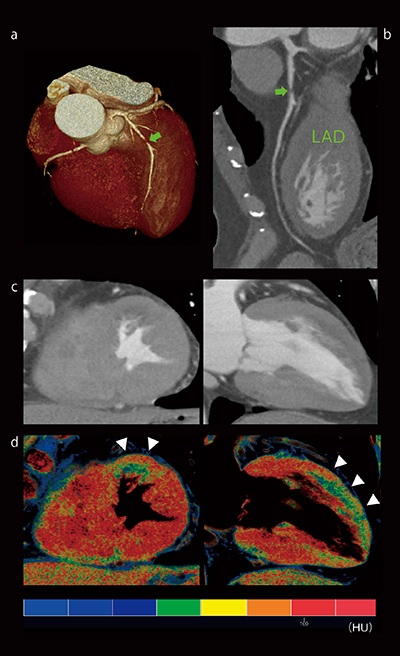

図1 心筋灌流評価

a:心臓VR画像

b:左前下行枝(LAD)CPR画像

c:グレイスケール(短軸像,長軸像)

d:VR画像(短軸像,長軸像)

50歳代,男性。LAD#6に高度狭窄を認める(a,b➡)。グレイスケール(c)では描出が不明瞭であるが,心筋内のわずかなCT値差を強調させたVR画像では前壁心内膜側に顕著な造影低下領域(d▽)を認める。造影低下領域は,狭窄病変による虚血領域を描出していることが考えられる。